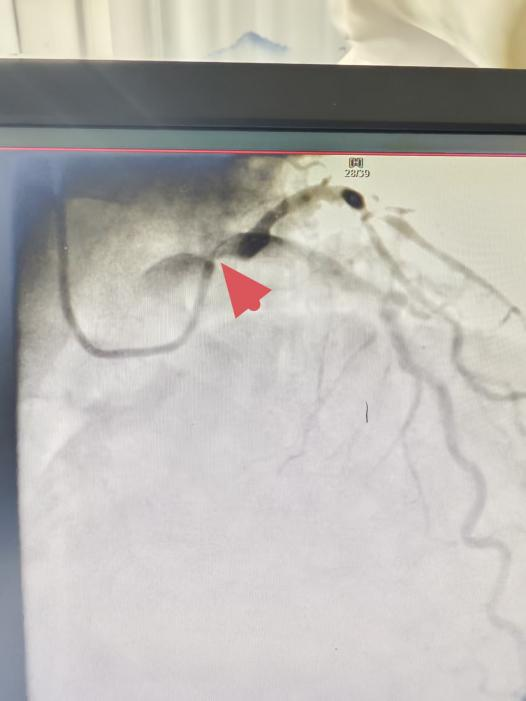

96岁“心”挑战!青岛西海岸第二医院心脏诊疗中心成功为超高龄患者实施高危介入手术

当96岁的管爷爷(化名)因反复胸闷胸痛来到青岛西海岸第二医院时,他的心脏正面临着“生死考验”——左主干开口85%狭窄伴重度钙化,这一被称为“心脏血管生命线”的病变,一旦进展为急性心梗,死亡率几乎接近1